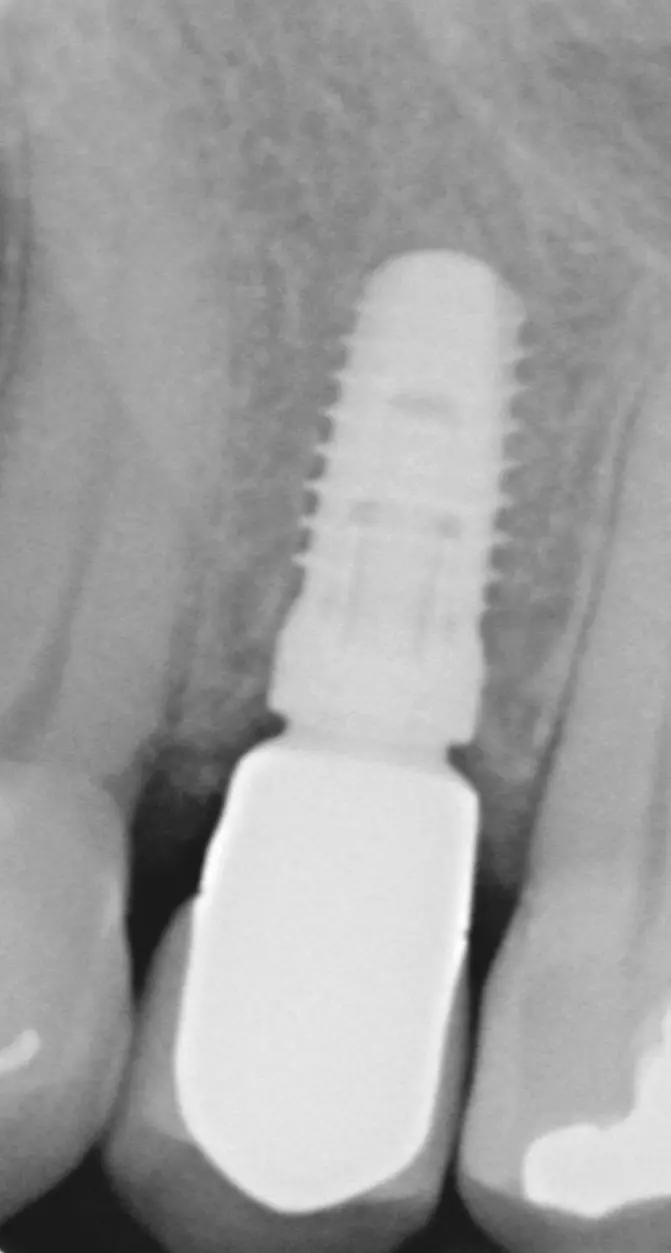

Bone-Level Implantate zeigten ein signifikant höheres Periimplantitisrisiko, wenn der Emergenzwinkel >30° betrug, im Vergleich zu den Bone-Level Implantaten, deren Abutment ein Emergenzwinkel von <30° aufwies (31,3% zu 15,1%). Bei Tissue-Level Implantaten konnte dieser Zusammenhang nicht nachgewiesen werden.

Wenn zusätzlich zu dem Emergenzwinkel auch noch das Emergenzprofil in die Analyse einbezogen wurde, zeigte sich bei einem Emergenzwinkel >30° in Kombination mit einem konvexen Emergenzprofil (Abb. 3) auf mindestens einer interproximalen Seite eine signifikante Erhöhung der Periimplantitisprävalenz von 37,8% (p=0,003).

30° in Kombination mit einem konvexen Emergenzprofil.“ class=“wp-image-26382″/>

30° in Kombination mit einem konvexen Emergenzprofil.“ class=“wp-image-26383″/>

Auch diese signifikante Erhöhung des Periimplantitisrisikos bezieht sich auf Bone-Level Implantate, nicht aber auf Tissue-Level Implantate. Es scheint, dass die reduzierte Hygienefähigkeit und die damit verbundene erhöhte Plaqueakkumulation für die erhöhte Periimplantitisprävalenz von Implantaten, die mit Abutments mit weitem Emergenzwinkel und konvexem Emergenzprofil versorgt sind, verantwortlich sind [11].